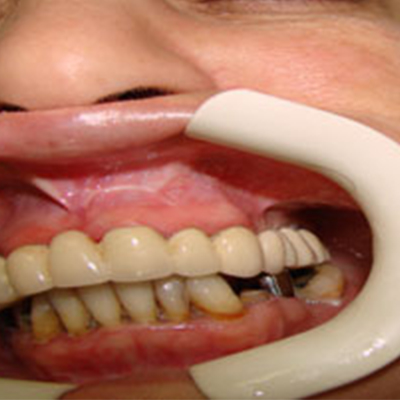

If you have lost several teeth, replacing them with dental implants is an excellent alternative to bridges or partials because your replacement teeth are not dependent on support from adjacent teeth and do not require the inconvenience of a removable appliance. Below are some examples of patients who chose dental implants to restore multiple missing teeth.

Individual crowns or a fixed bridge are permanently secured to the implants, while removable overdentures are held in place by a bar and clip. Below are some examples of different types of restorations for patients who were missing all of their upper or lower teeth